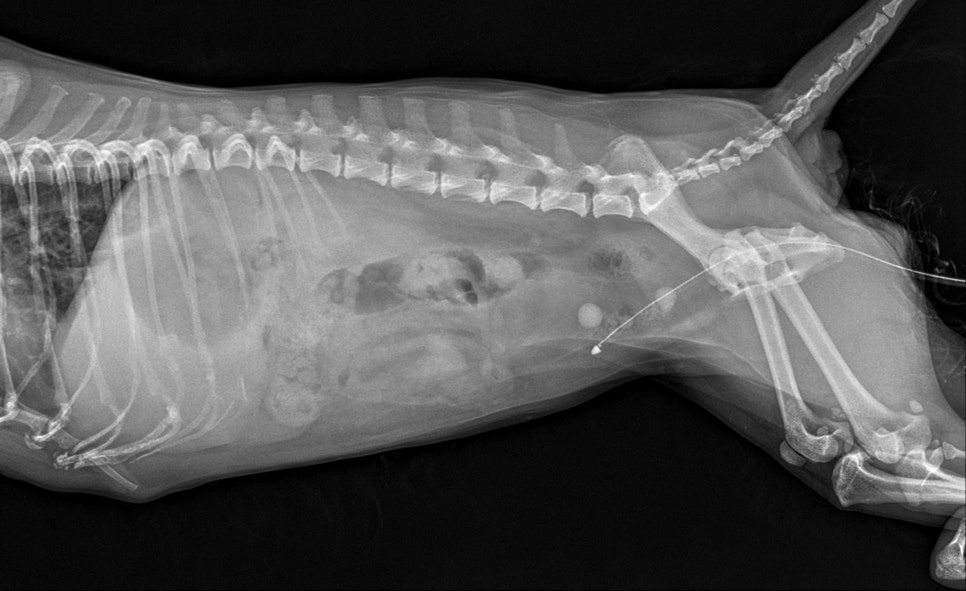

수술 후 방사선 사진 / 출처: 24시 온숲동물의료센터

수술 후 방사선 검사에서 결석이 모두 제거된 상태로 확인되었습니다. 수술 직후부터 의료진이 염증 수치와 전신 상태를 면밀히 관찰하며 회복을 도왔습니다. 며칠간의 집중 케어 후 염증 수치가 정상 범위로 회복되었고, 강아지도 안정된 모습으로 퇴원했습니다.현재는 소변 배출이 원활하고 전반적인 상태가 호전된 모습을 보이고 있습니다.